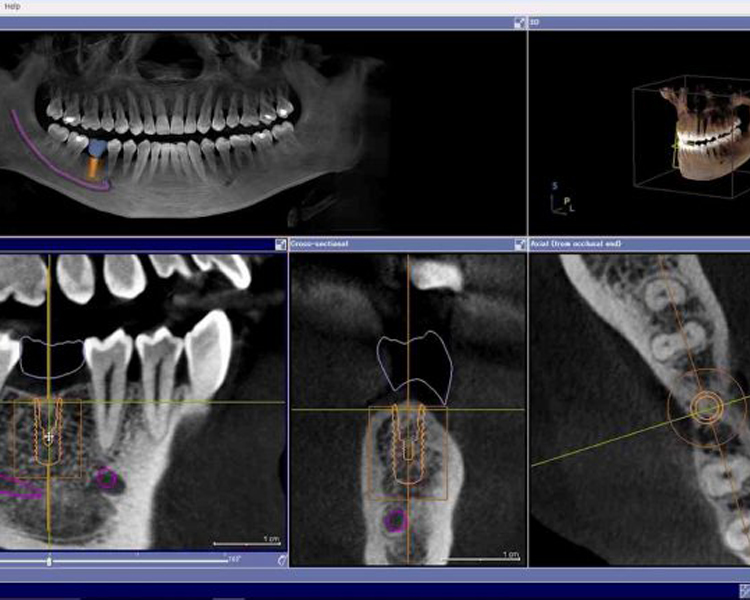

正確なインプラント治療のために

CTスキャナー+3D画像診断・

サージカルガイドを導入

CT撮影した画像を用いて骨形成を正確に把握し、インプラント埋入位置の検討を行うことによって安全性と審美性を第一に考えた手術を実現します。

インプラントガイド